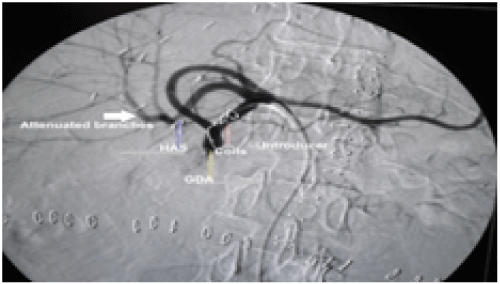

Figure 1: (A) A patient with HAT and aneurysm. (B) The patient underwent coiling of aneurysm and stenting of HAT.

View Figure 1

Lastly the patient with late IVC tear died intraoperative during operation for HCC recurrence (Figures 1, Figures 2, Figures 3, Table 3).